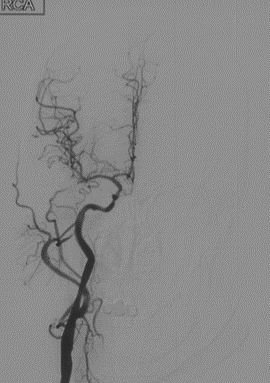

辅助检查(DSA)

R-CA

波科支架怎么样径技-弓上病例大赏|第210期·右侧颈内动脉球囊扩张术+支架植入术_https://www.jmylbn.com_新闻资讯_第12张

• 病例特点:右侧颈内动脉C1段重度狭窄,致远端供血区域脑梗死,手术指征明确;